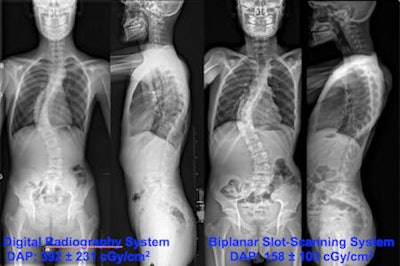

Neutral standing radiographs of 18-year-old man demonstrates dextroscoliosis at the thoracic level (Cobb angle: 65°) and levoscoliosis at the lumbar level (Cobb angle: 55°). Standard digital radiographs on the left side were obtained at the first consultation. Biplanar radiographs on the right side were requested six weeks later prior to surgery. Additional secondary 3D reconstructions of the biplanar radiographs were provided to the spine surgeon to plan the operation. All images courtesy of Dr. Tobias Dietrich.This cost analysis may prove useful for imaging departments considering purchasing a biplanar x-ray unit (EOS Imaging), according to lead author Dr. Tobias J. Dietrich and colleagues.

Because of its design, the biplanar x-ray system enables diagnostic quality images to be acquired at lower radiation levels. As a result, the dose area product was lower than that of the standard DR system. A whole spine image generated a dose area product of 158.4 cGy/cm2 compared with 392.2 cGy/cm2 when a standard DR system was used.